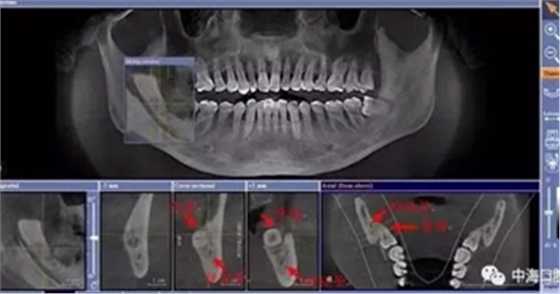

由于智齒的生長(zhǎng)位置特殊,導(dǎo)致了拔除難易不同,如智齒出現(xiàn)橫著長(zhǎng)或者靠近牙神經(jīng)的話,則難度會(huì)較高,一般人只需拍個(gè)口腔全景片,但相對(duì)于智齒靠近神經(jīng)管的情況,還可能需要拍CT,這都很考驗(yàn)牙醫(yī)的技術(shù)。